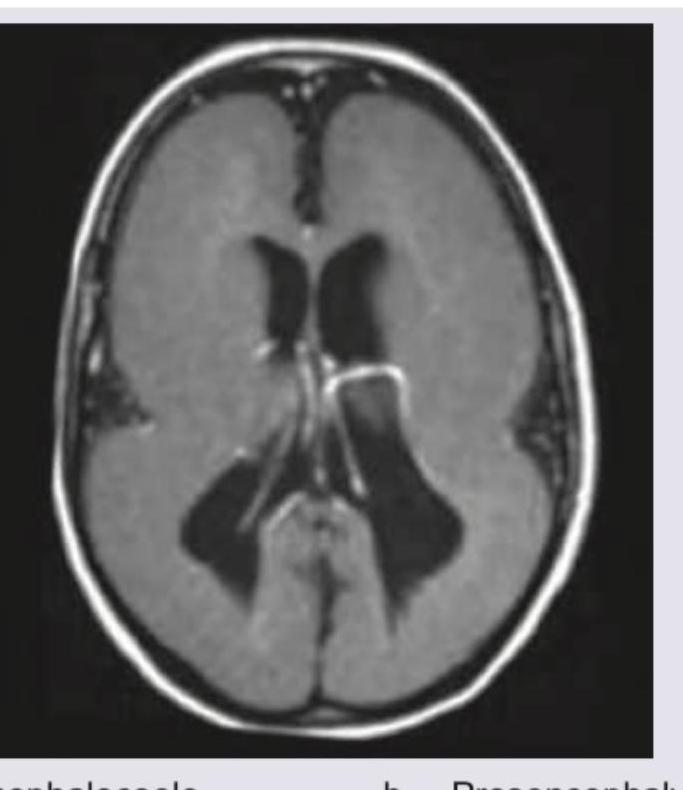

Identify the following abnormality?

Explanation: ***Schizencephaly*** - The image shows a **cleft-like defect** extending from the pial surface to the ventricle, lined by **gray matter**, which is characteristic of schizencephaly. - This typically results in communication between the **subarachnoid space** and the **ventricular system**. *Encephalocoele* - An encephalocoele is a **protrusion of brain tissue** and meninges through a defect in the skull, which is not depicted in this image. - It usually presents as a **sac-like bulge** on the head, often in the occipital or frontal regions. *Prosencephaly* - This term usually refers to the malformation spectrum associated with **holoprosencephaly**, characterized by a failure of the prosencephalon (forebrain) to properly divide. - Features include **fusion of the cerebral hemispheres**, a single ventricle, and facial anomalies, not a cortical cleft as seen here. *Lissencephaly* - Lissencephaly is characterized by a **lack of gyri and sulci** (smooth brain surface) or abnormally broad and flattened gyri, leading to a thickened cortex. - The image clearly displays presence of gyri and sulci, although with an additional unusual cleft, ruling out a primary diagnosis of lissencephaly.